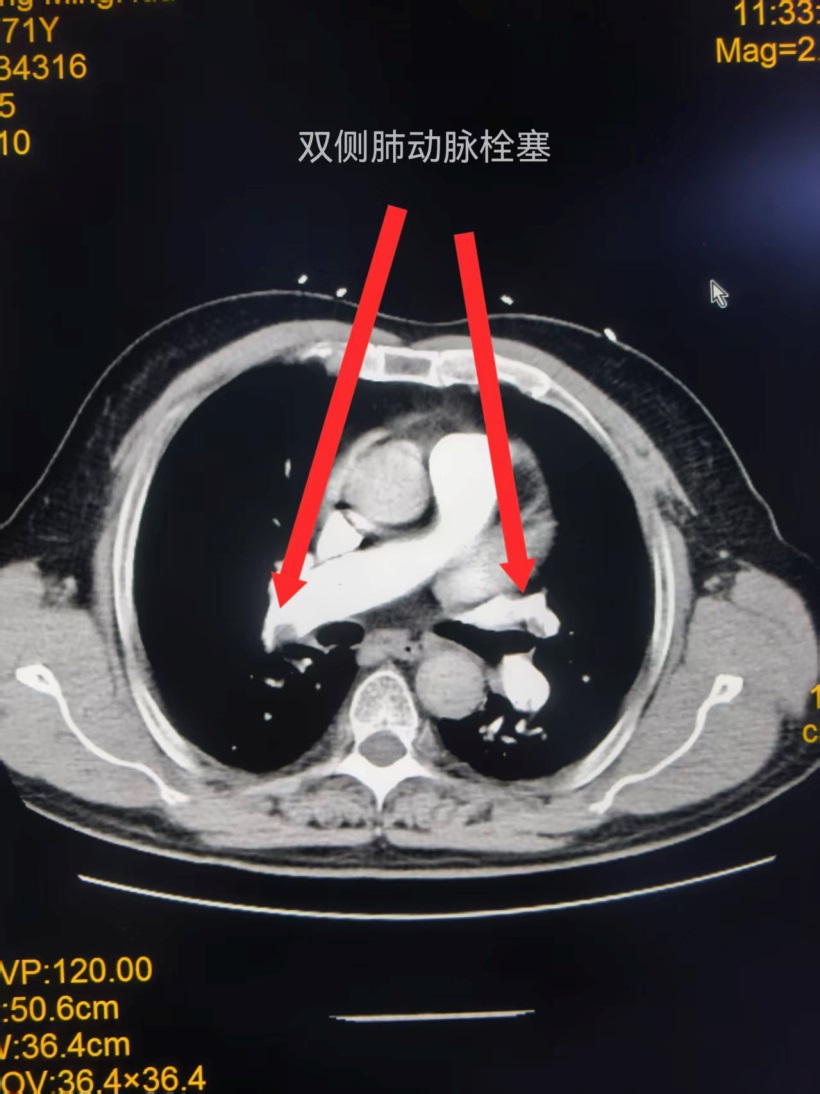

无缝衔接救急症 精准配合护生命——玉林市红十字会医院多团队紧密配合成功完成急诊重症肺动脉取栓术